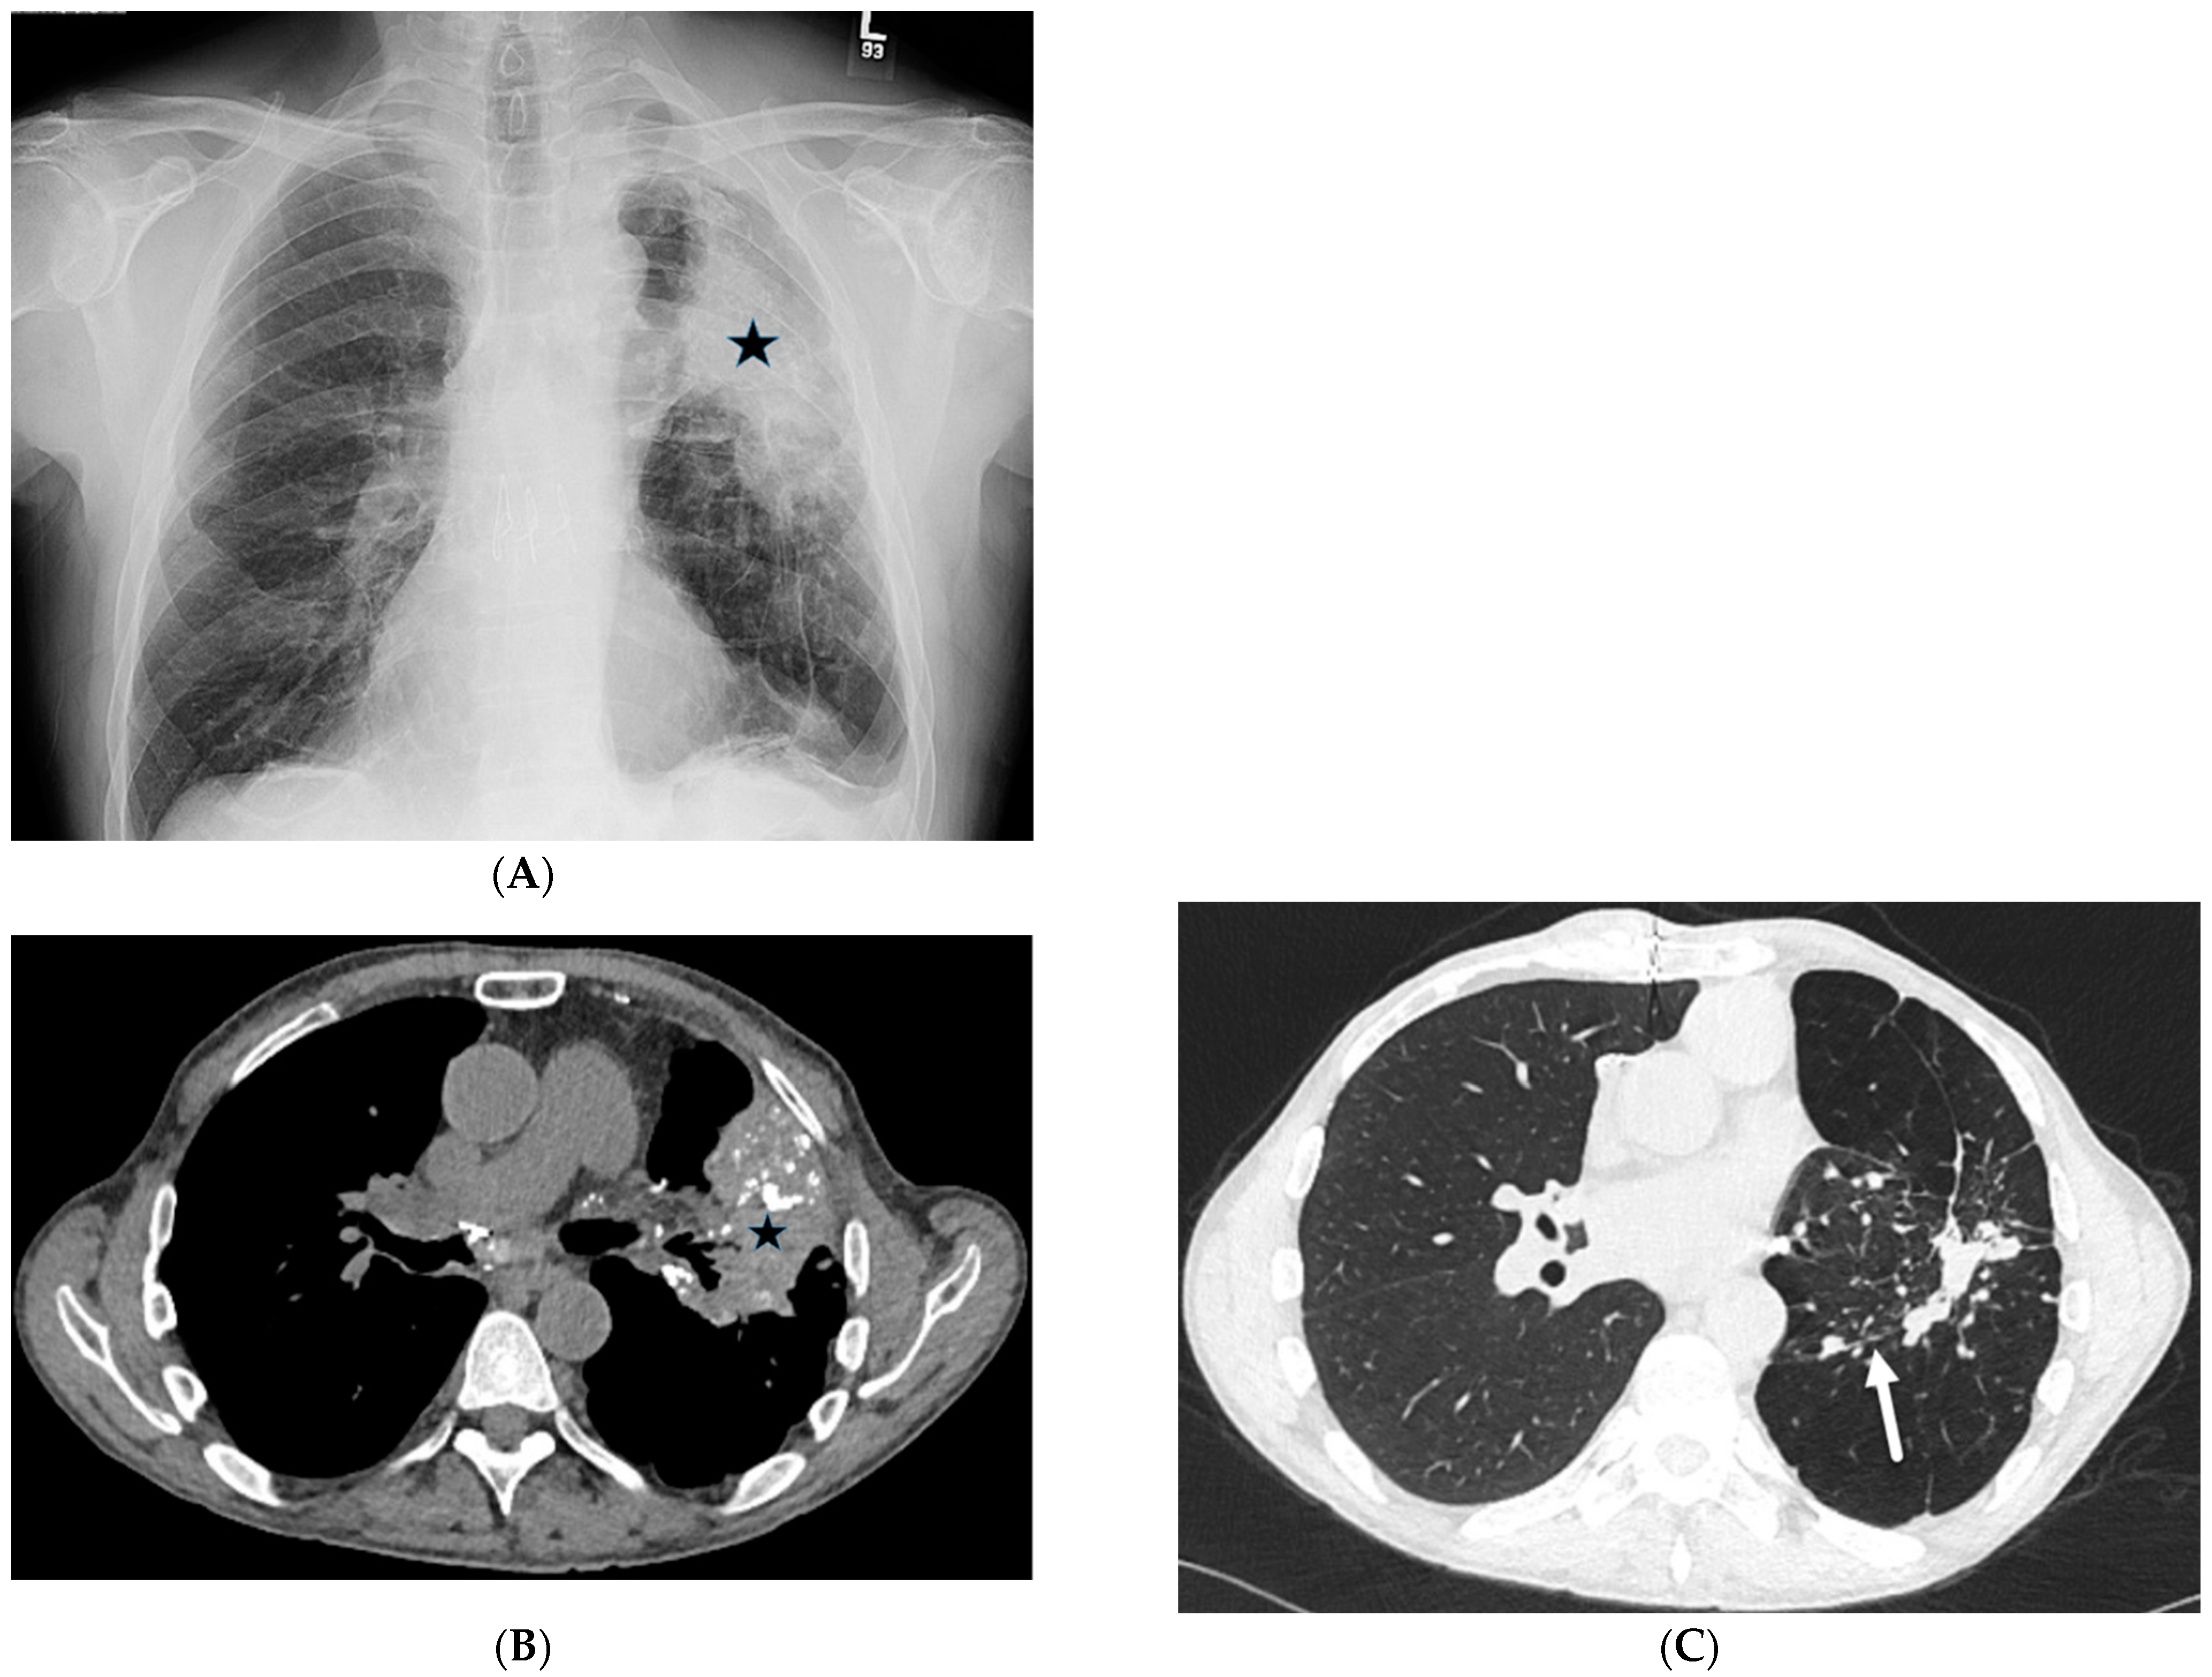

4.7. Pulmonary Vein Stenosis (PVS)

- Holmes, D.R.; Monahan, K.H.; Packer, D. Pulmonary vein stenosis complicating ablation for atrial fibrillation: Clinical spectrum and interventional considerations. JACC Cardiovasc. Interv. 2009, 2, 267–276. [Google Scholar] [CrossRef] [PubMed]